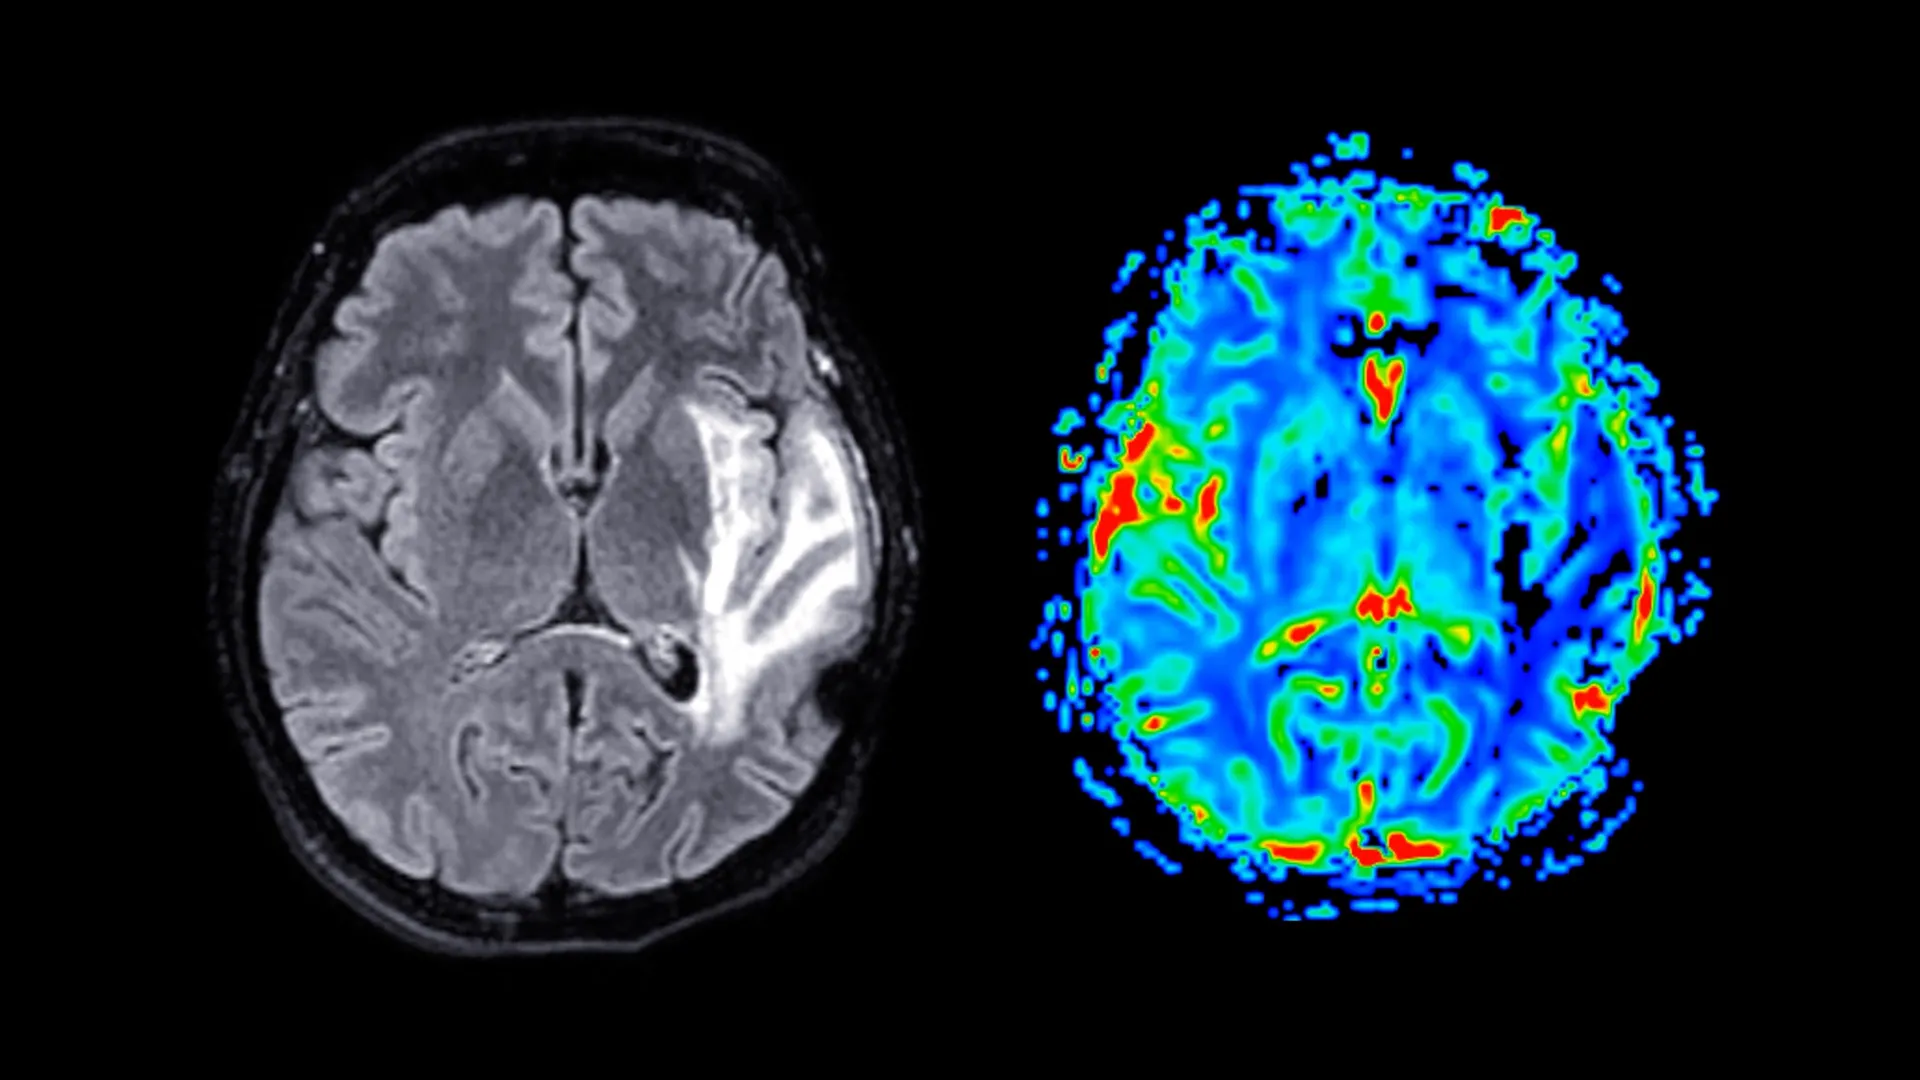

A demência é um problema crescente de saúde pública global e atualmente não há cura. As pessoas afetadas por esta condição apresentam um grave declínio nas capacidades mentais, incluindo memória, pensamento e raciocínio, o que pode interferir significativamente na vida diária.

A demência refere-se a um grupo de distúrbios cerebrais e não a uma única doença. As formas mais comuns são a doença de Alzheimer, a demência vascular e a demência mista. Essas condições danificam gradualmente as células nervosas do cérebro e os sintomas pioram com o tempo. À medida que a doença progride, as pessoas podem enfrentar mudanças na memória, na linguagem, na resolução de problemas e no comportamento.